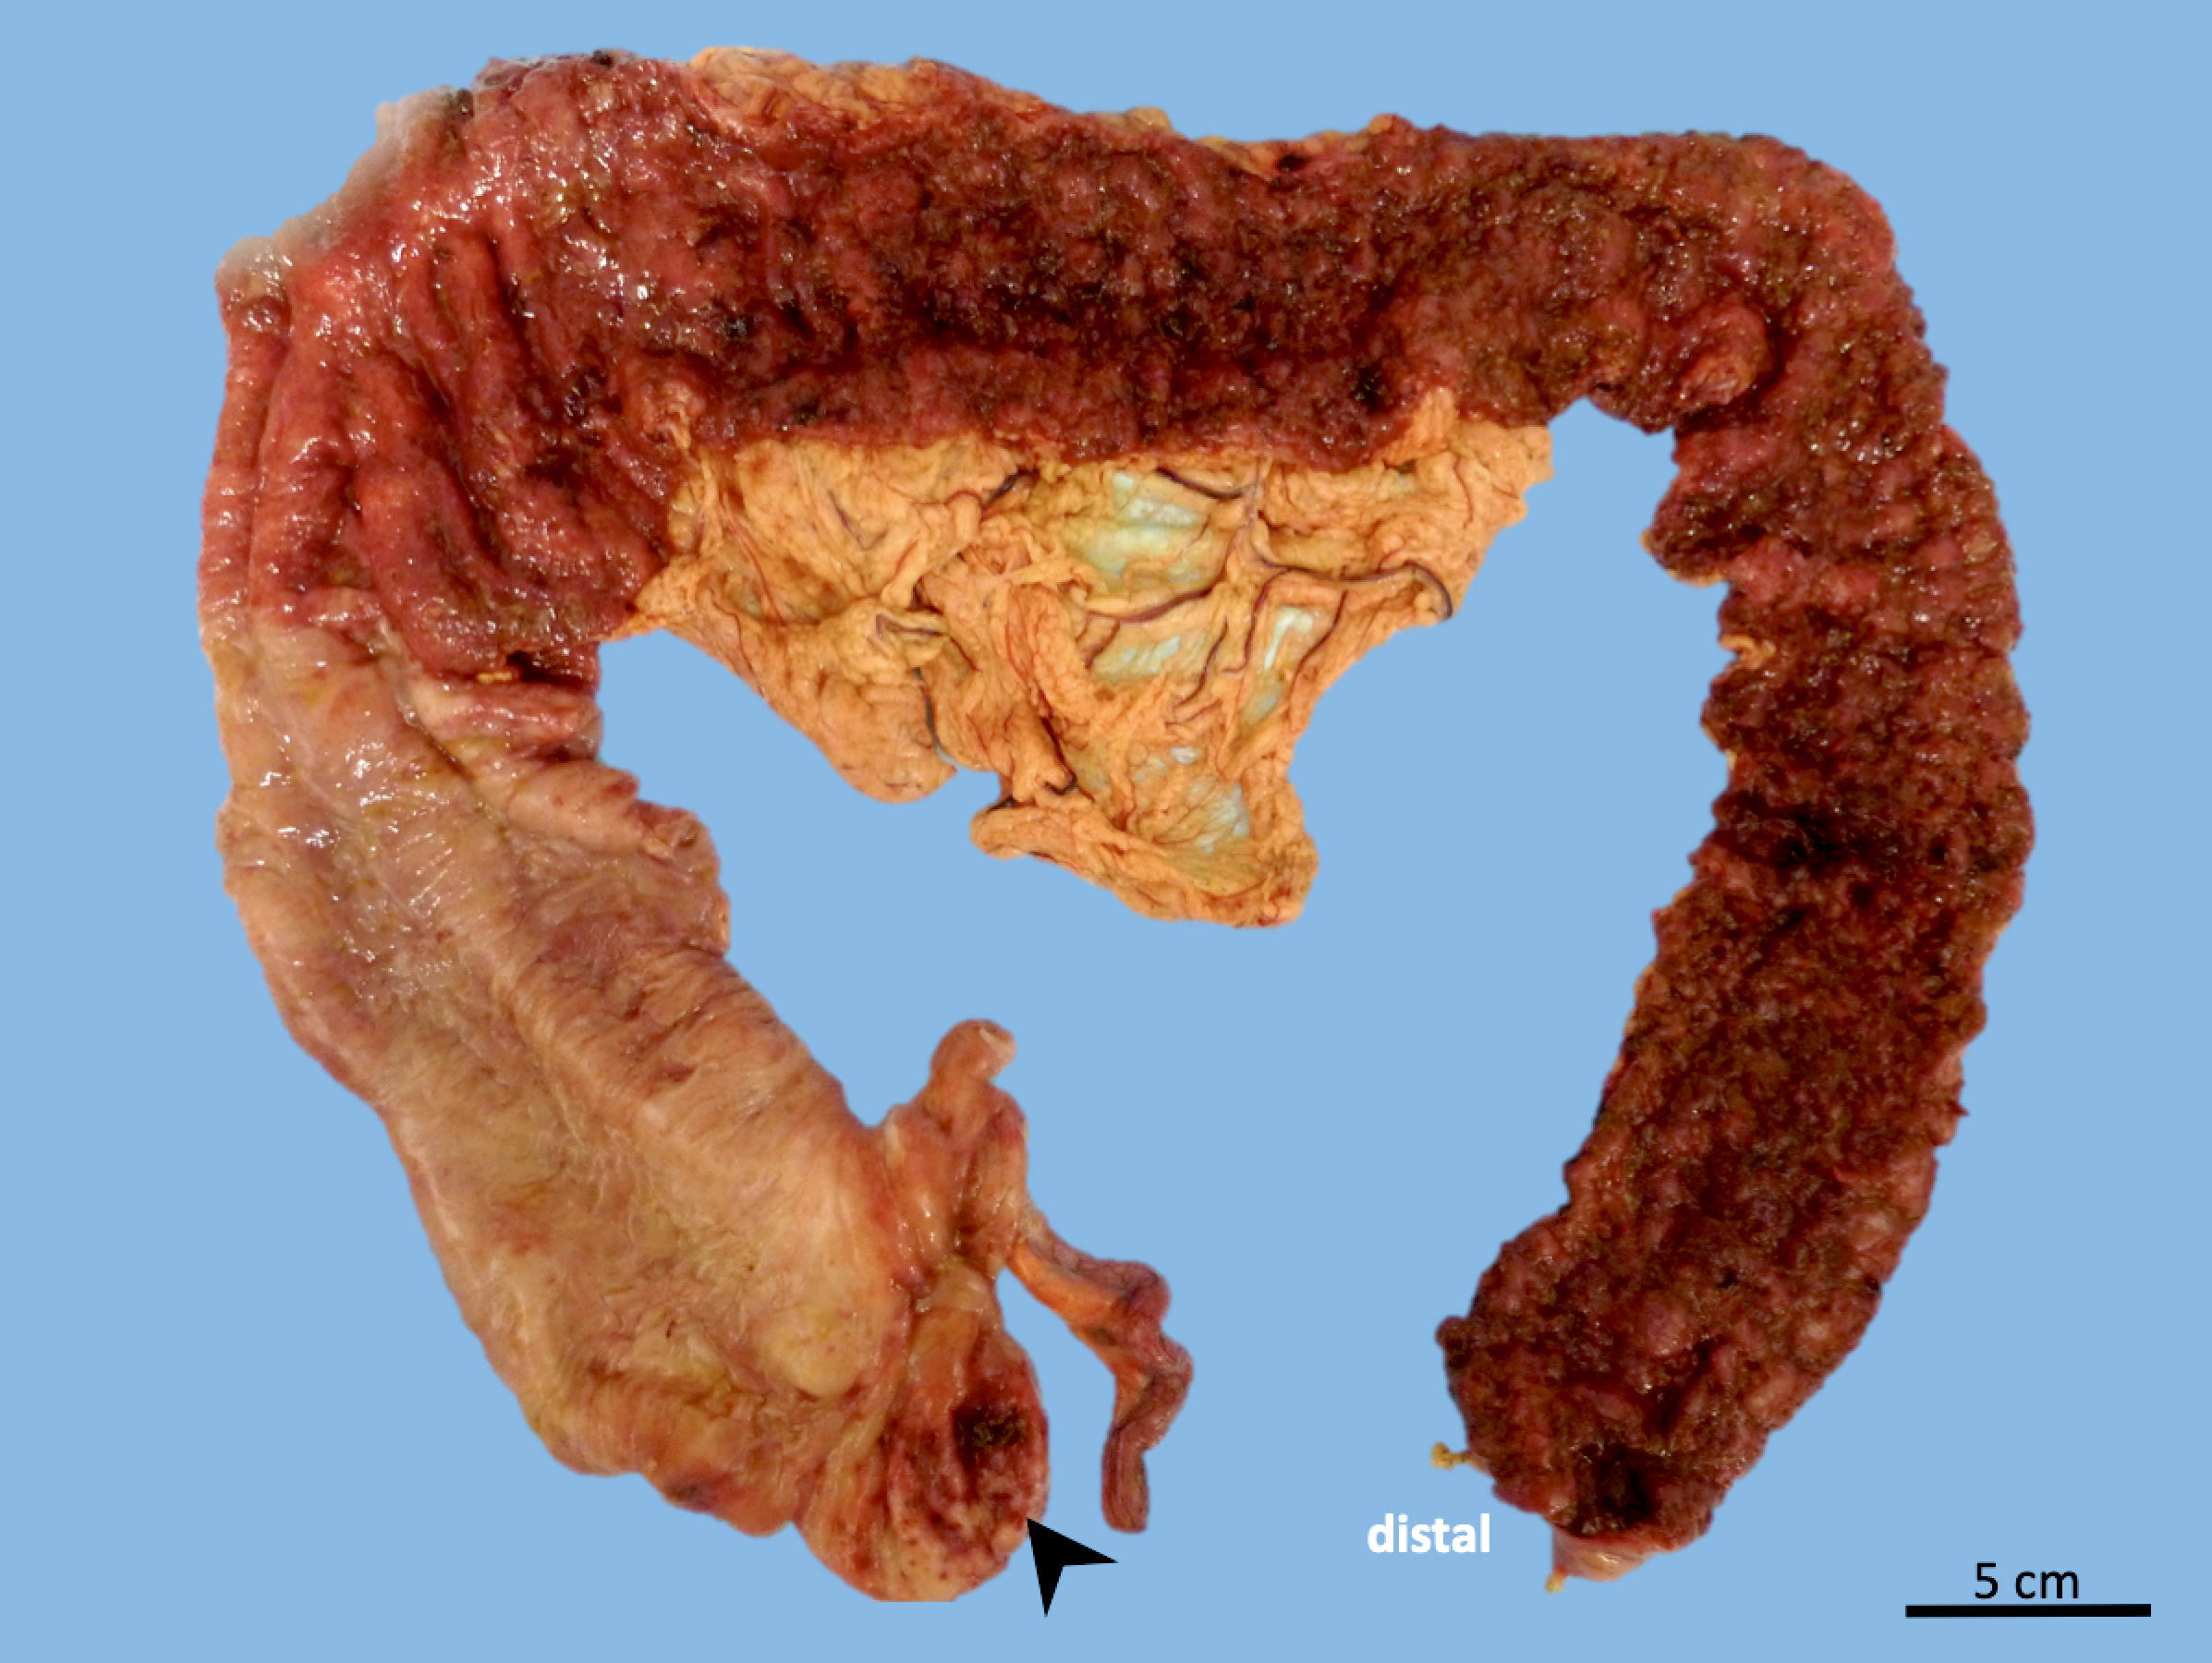

A 26 year old woman with no significant past medical history is found to have severe colitis and undergoes total abdominal colectomy. The gross examination of the resection specimen reveals a predominantly left sided colitis with discontinuous involvement of the cecal and periappendiceal mucosa, as shown in the image above. Microscopic evaluation demonstrates a mucosa based, active chronic colitis without evidence of transmural inflammation. Several nonnecrotizing epithelioid cell granuloma associated with ruptured crypts are identified. Which of the following is true regarding the patient’s pathologic diagnosis?

The photograph shows a total abdominal colectomy specimen with a predominantly left sided colitis and discontinuous involvement of the cecal or periappendiceal mucosa. The gross and microscopic findings are convincing for a diagnosis of ulcerative colitis. It is well documented that patients with left sided ulcerative colitis may have discontinuous involvement of the periappendiceal or cecal mucosa, known as a cecal patch. A diagnosis of IBD, indeterminate type should be avoided when dealing with well recognized variants of IBD, such as ulcerative colitis with cecal patch and superficial (ulcerative colitis-like) Crohn's disease. Nonnecrotizing epithelioid cell granulomas associated with ruptured crypts (cryptolytic granulomas) are known to occur in cases of ulcerative colitis and often result in diagnostic difficulties; however, this finding should not preclude a diagnosis of ulcerative colitis.